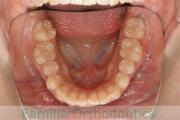

No.22V-029

- 叢生

- 上顎前突

- 19歳

- 男性

- 上:

- 8448

- 下:

- 主な使用装置:

- FEA 022

- 治療にかかった費用:

- 92万円

でこぼこを治したいということで来院されました。上下左右から親知らずも第一小臼歯も抜歯が必要で、歯科矯正アンカースクリューを併用して大臼歯を後ろに引っ張りながらの治療でした。3年弱、35回程度の通院が必要でした。

叢生が著しく、後戻りのリスクがあります。またアンカースクリューが必須のため、もしもスクリューが安定しないと、治療が難しく長くなってしまう恐れがありましたが、幸い脱落は見られませんでした。

- ≫治療前

上顎

下顎

- ≫治療後